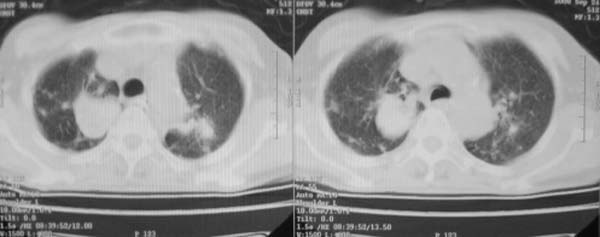

女,78岁,声嘶月余,否认有既往病史,有粉尘接触史10年。

双上肺结节融合影,周围有纤维条索影,结合粉尘接触史,首先考虑尘肺。双侧颈部有增大淋巴结,有声嘶表现,肺癌淋巴结转移不能排除。可结合颈部淋巴结活检。

尘肺合并肺癌。

肺癌伴纵膈、双颈部淋巴结转移;尘肺。

右上肺癌伴肺内转移及纵隔淋巴转移 左上肺结核 图像有点模糊